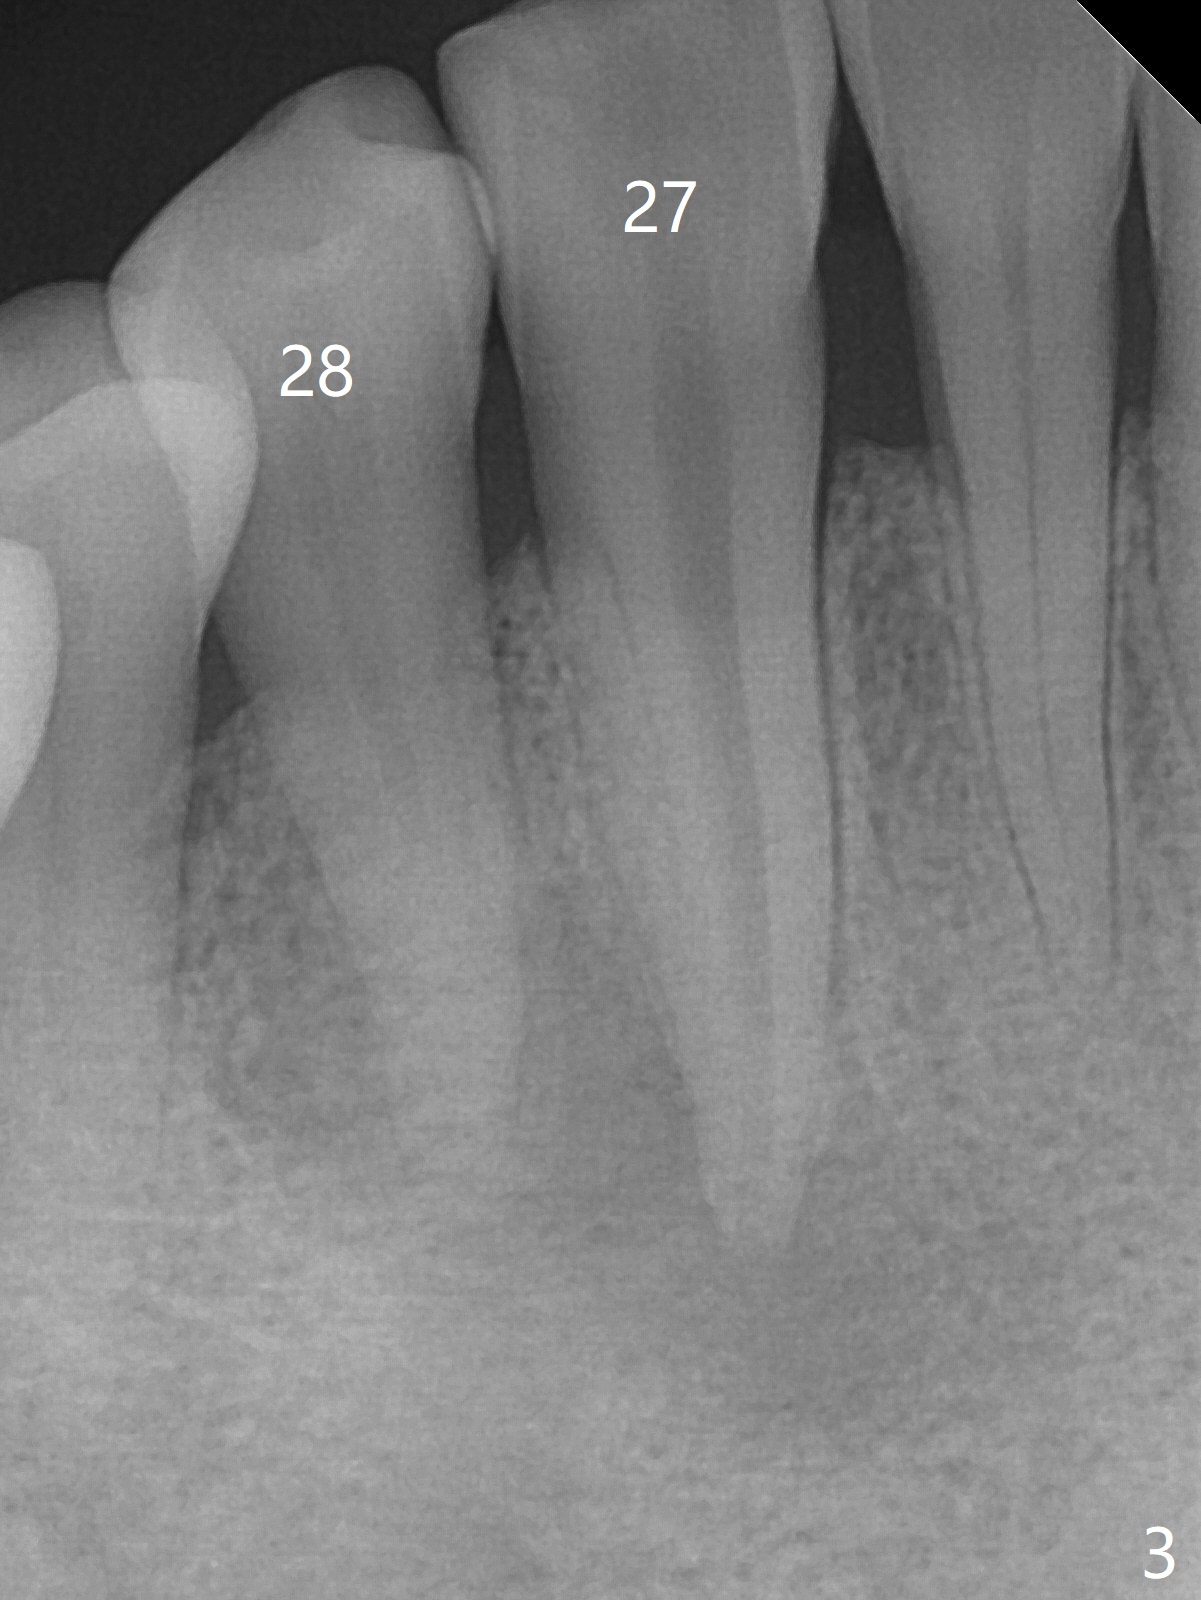

A 47-year-old woman with autoimmune hepatitis has a fistula distal to the tooth #28 (Fig.1). Periapical radiolucency appears to involve the teeth #27 and 28. Which is the infected tooth? Treatment plan?